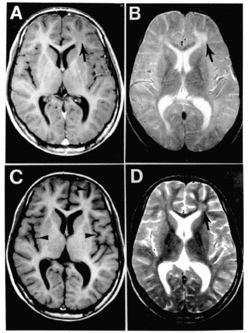

Subacute sclerosing panencephalitis. | |

"SSPE is suspected in young patients with dementia and neuromuscular irritability. EEG, CT or MRI, CSF examination, and measles serologic testing are done. EEG shows periodic complexes with high-voltage diphasic waves occurring synchronously throughout the recording. CT or MRI may show cortical atrophy or white matter lesions. CSF examination usually reveals normal pressure, cell count, and total protein content; however, CSF globulin is almost always elevated, constituting up to 20 to 60% of CSF protein. Serum and CSF contain elevated levels of measles virus antibodies. Anti-measles IgG appears to increase as the disease progresses. If test results are inconclusive, brain biopsy may be needed."